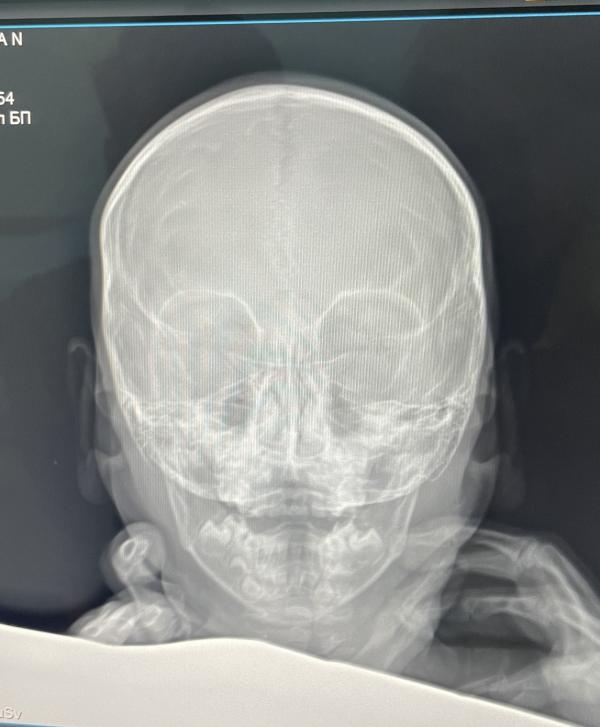

Лежим в больнице. Младшая упала с качели и ударилась головой.

Примчались в приемный покой. Кости целые, гематом нет. Положили до утра на всякий случай. Один раз дочу вырвало. Плачет, что хочет домой. Говорит «уже не болит, поехали отсюда».